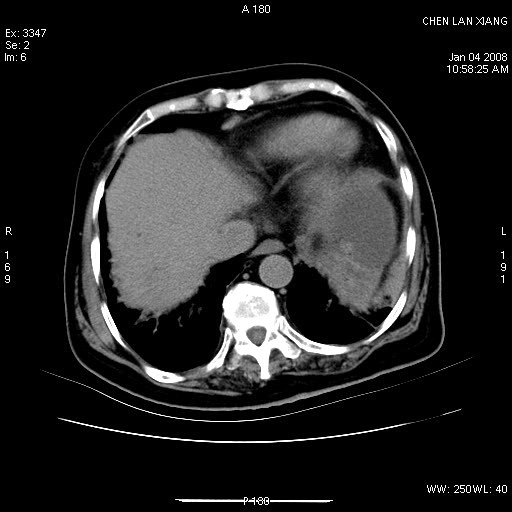

女,76岁,腹痛3-4天,b超示:肝内实性肿物,胆囊强回声,胆总管扩张.

考虑:1、胆总管下端结石伴梗阻性肝内外胆管扩张(肝左叶外侧段肝内胆管多发结石、胆管炎);

2、肿囊癌累及肝,不除外 黄色肉芽肿性胆囊炎。

1 胆总管末端结石伴肝内胆管结石,肝内外胆管扩张。2 胆囊扩大,胆囊壁不规则增厚,内见软组织密度影。考虑:慢性胆囊炎,不除外胆囊癌!

ct所见:1、 肝内胆管结石,肝内外胆管扩张。低位胆道梗阻,胆总管下端结石;2 胆囊扩大,胆囊壁不规则增厚

考虑:胆总管下端结石并肝内外胆管扩张,肝内胆管结石;

1)胆囊癌伴肝脏转移。2)胆总管下端结石、肝内胆管结石伴肝内外胆管扩张。